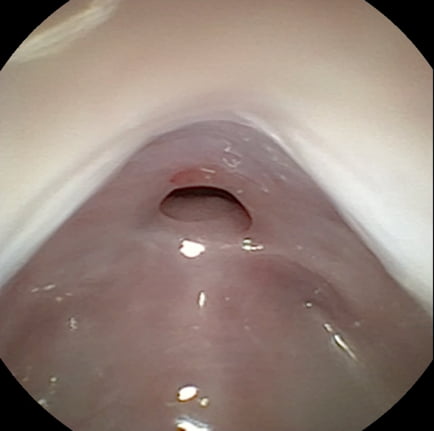

鼻咽頭狭窄の治療前と治療後